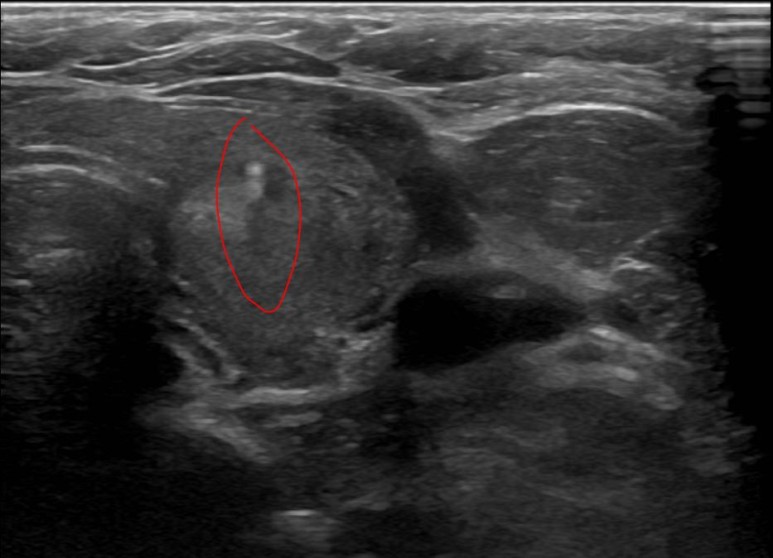

양성 결절로 진단받은 증례 130대 초반의 여성으로 오른쪽 갑상선에 2.7cm 결절이 관찰된다.

세침 흡인 검사 실시

베세다 시스템II에서 악성 가능성이 3% 미만인 양성 결절로 진단 받았습니다.양성 결절로 진단된 증례 2